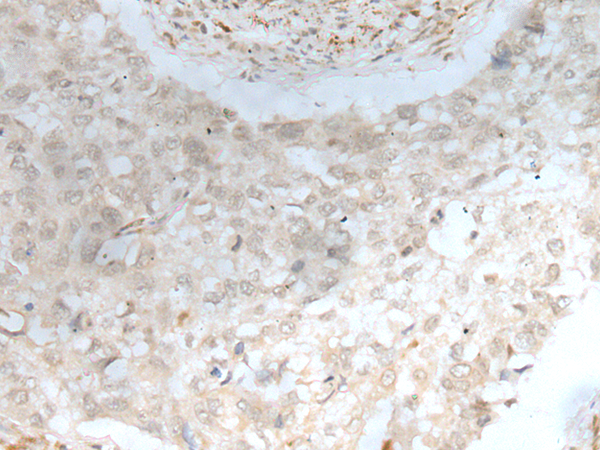

IHC positive control: |

Human esophagus cancer and human lung cancer |

IHC Recommend dilution: |

20-100 |